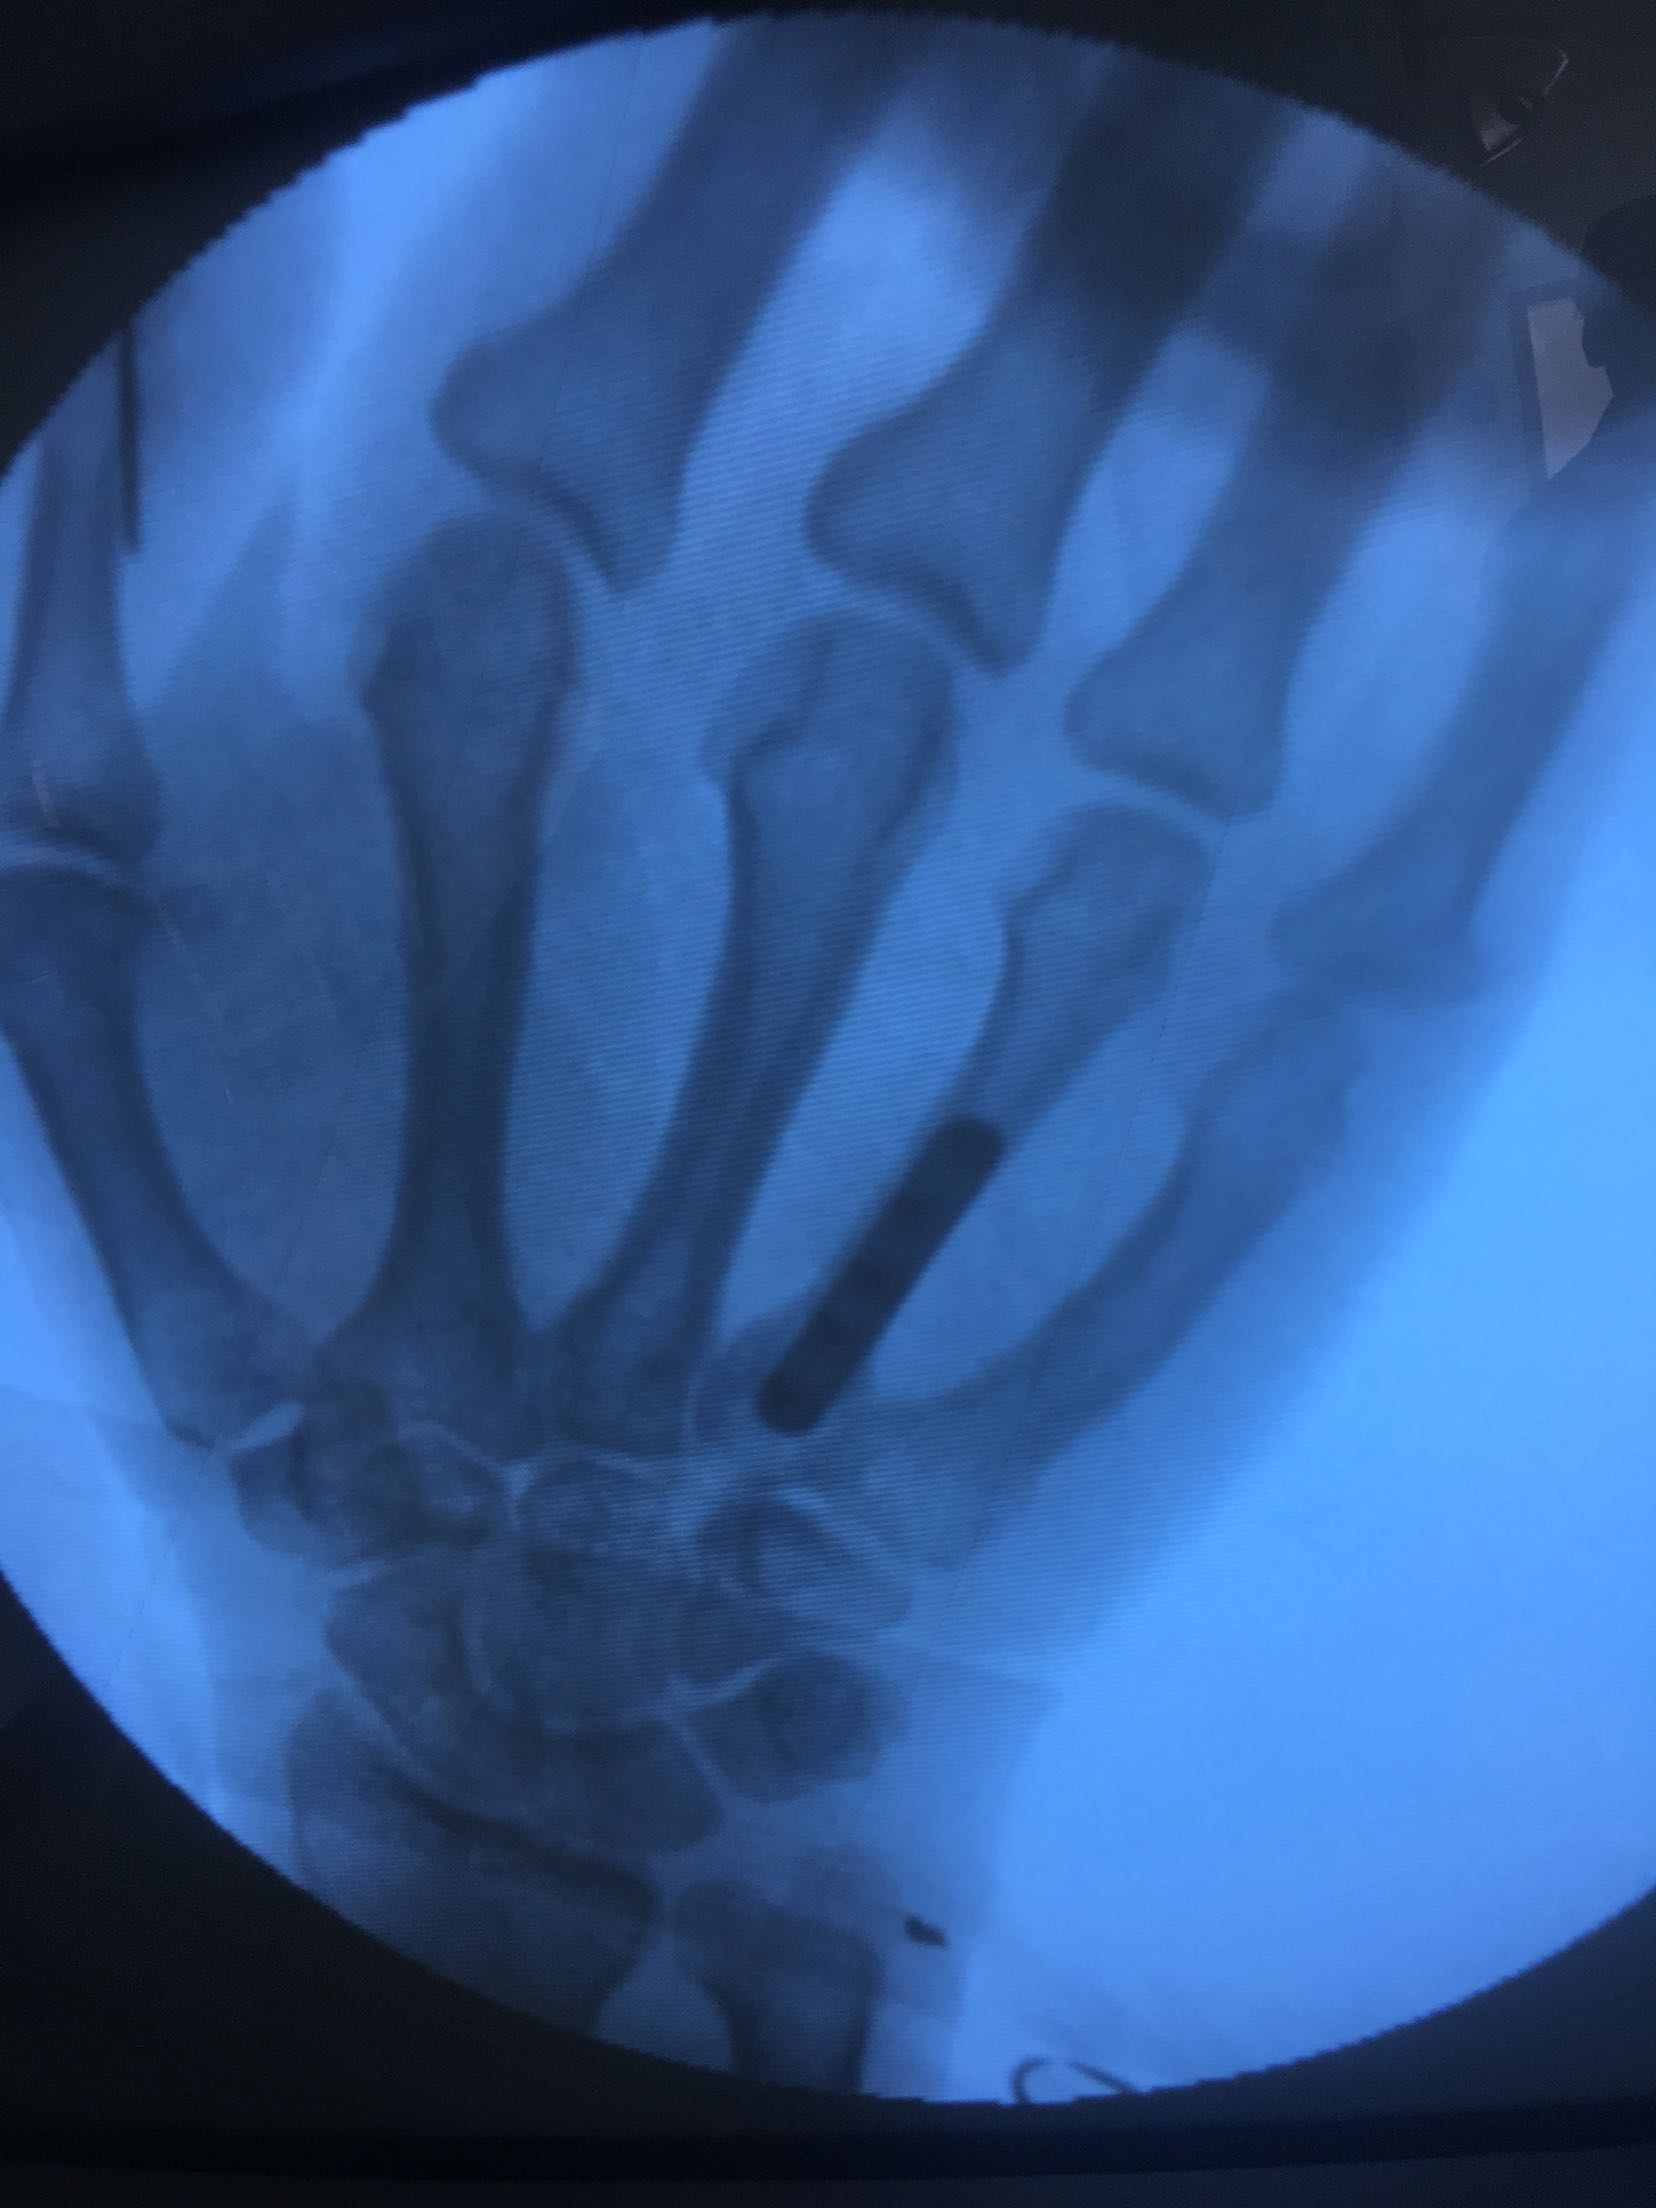

患者,男,51岁,电钻挤打伤后右手,肿痛,活动受限1小时入院。既往身体健康,无特殊不良嗜好。

右手大拇指呈锤状改变,掌背侧肿胀明显,皮色发红,皮温高,局部压痛,第四掌骨纵叩痛阳性,局部活动障碍,末梢血运感觉正常。

积极术前准备,在臂丛麻醉下行锤状指伸指功能重建术,掌骨骨折切复内固定术,术后抗炎,消肿对症处理。<img src=https://pub-voice-video.medlinker.com/9129333F-3928-47F0-B39A-978756FECFAD><img src=https://pub-voice-video.medlinker.com/945D4FD6-D0B7-41EF-ABB0-C2940D6C2E54><img src=https://pub-voice-video.medlinker.com/2F847276-23A8-4CAF-BF99-1828976F7BAD><img src=https://pub-voice-video.medlinker.com/2996EABA-9281-4CC0-8612-66A515AC6472><img src=https://pub-voice-video.medlinker.com/D3EFB6D4-D26D-4778-B65E-2D52DD5235E7><img src=https://pub-voice-video.medlinker.com/9197F543-FC48-48BB-BA43-DDBEEE8749C0><img src=https://pub-voice-video.medlinker.com/109E9BC2-A473-4E71-B880-027E2D1DF300>